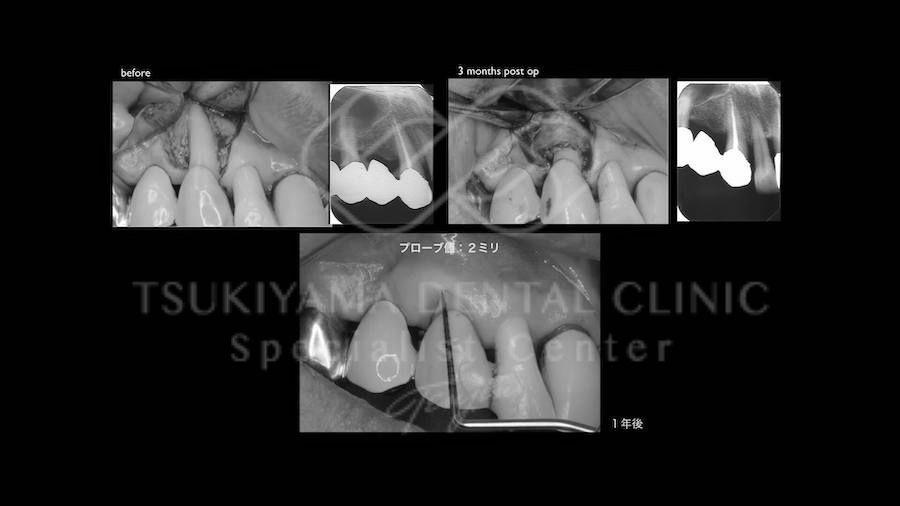

歯周病によって破壊された歯ぐきや歯を支える骨(歯槽骨)を再生材料(成長因子、人工骨移植、コラーゲン膜)を用いて再生、回復させる外科的治療法です。

歯周病でダメになった歯をどうしても残したい方、歯ぐきや歯槽骨を元に戻して歯の寿命をしっかり伸ばしたい方に適応される治療方法です。

「エムドゲインと骨移植を利用した再生治療」(豚由来 エナメルマトリックスタンパク)

術前と術後の比較